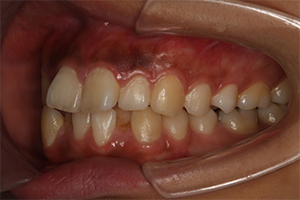

矯正治療のCASE 04

Before

After

- 主訴

- 歯並びがガタガタしていて清掃しにくい

- 治療内容

- ラビアル矯正(表側)

抜歯あり

- 治療費用

- 88万円~(税込)

- 治療期間

- 20か月

【リスク・副作用】

歯の痛み、口内炎、歯磨きがしにくいことによるむし歯や歯周病のリスク、歯根吸収や歯の変色、後戻りなどの副作用があります。